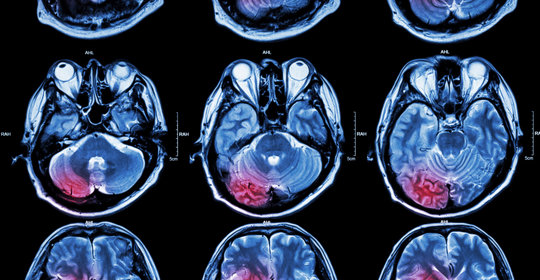

腦中風後遺症的症狀、前兆、治療和預防

腦溢血後遺症的症狀、前兆、治療和預防

腦血管破裂後遺症的症狀、前兆、治療和預防

腦梗塞後遺症的症狀、前兆、治療與預防

腦出血引流手術後遺症的症狀、前兆、治療和預防

腦缺氧後遺症的症狀表現、前兆、治療及預防